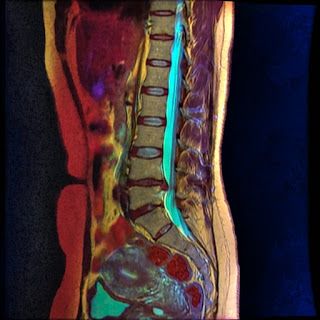

Классическая магнитно-резонансная томография разных отделов позвоночника пришла на смену травматичному рентгеновскому методу – миелографии. До массового распространения МРТ грыжи межпозвонковых дисков, сужение канала позвоночника выявлялись только на рентгеновских снимках после введения контрастного бария в пространство спинного мозга.

Безопасность, высокая специфичность, достоверность, доступная стоимость МР-сканирования при верификации патологии мягких тканей сделали метод предпочтительным вариантом изучения позвоночного столба.

Полученные снимки представляют собой серию послойных изображений определенных отделов позвоночника с шагом в 3-4 мм, которые врач-рентгенолог сохраняет на своем компьютере, а затем переносит на диск или любой другой цифровой носитель, который потом выдается пациенту.

Выбор вида мрт позвоночника для выявления определенного заболевания должен осуществляться врачом, который будет выдавать результат исследования. Важен правильный выбор режима сканирования: на T2 взвешенных томограммах хорошо визуализируются хрящевые структуры, а при сочетании T1 и T2 последовательностей удается изучить мягкотканые и водные компоненты.